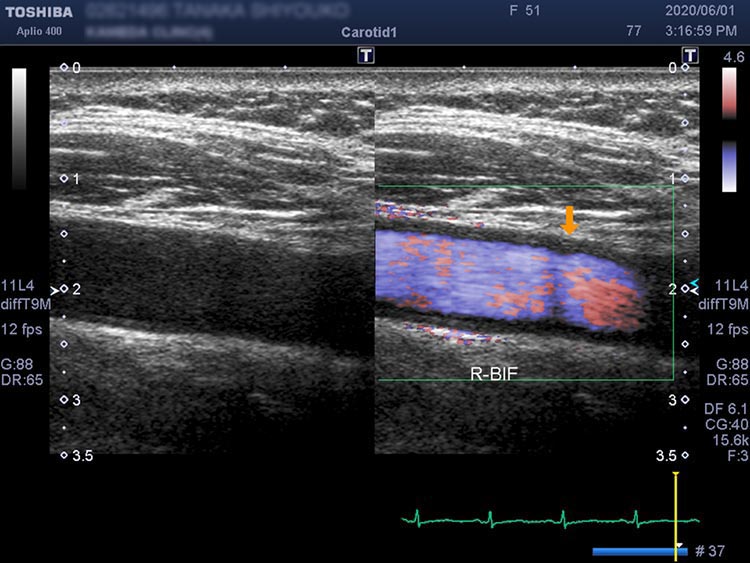

脳梗塞や脳出血の急性期の治療が終わったあと、再発予防のために治療の継続が必要となります。脳血管障害の背景には生活習慣病があることが非常に多く、適切な管理が必要になります。当院では専門医が再発予防のための生活習慣病の管理や専門的な超音波検査を定期的に実施可能です。